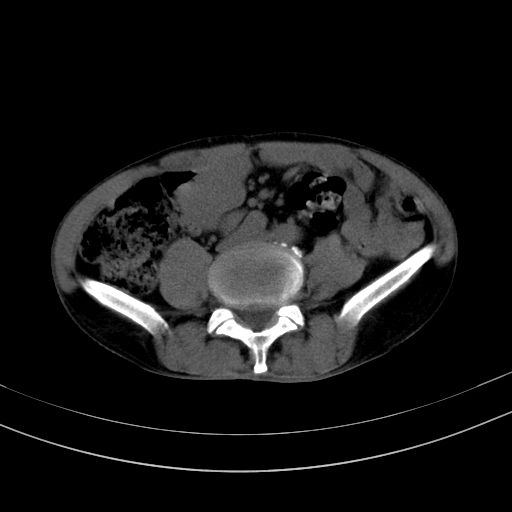

以下是引用37度在2010-1-9 14:37:00的发言:[br]1.双肾囊肿,左肾积水结石,.胆总管轻度扩张;[br]2.病灶在腹膜外,考虑纤维瘤。

以下是引用dyqct在2010-1-9 17:56:00的发言:[br]考虑:1.双肾囊肿,左肾积水结石、旋转不良。[br] 2.右侧腹直肌血肿或纤维瘤。[br]肠道准备不好。做个增强。